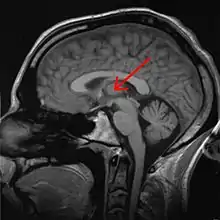

la flèche indique le thalamus. (sens 1)

- (Anatomie) Structure paire d'origine diencéphalique située de part et d'autre du troisième ventricule dont il constitue les parois latérales. Il sert à filtrer les informations qui arrivent au cortex cérébral.